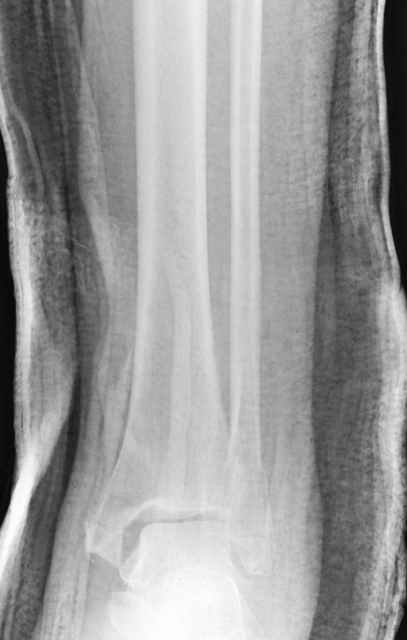

На прямой проекции послеоперационного Рг макроскопически все выглядит очень анатомично, при микроскопическом ( :-)) ) рассмотрении можно все-таки заметить вальгизацию тарана, суставная щель в латеральном отделе сустава несколько уже , чем в медиальном при отсутствии латерального смещения тарана. У меня был аналогичный случай (без LISS , без мини доступа) с вальгусным наклоном тарана при восстановленном ankle mortise при последовательном наблюдении с интервалами в 6-8 недель в послеоперационном периоде отмечалось прогрессирующее сужение суставной щели в латеральном отделе сустава, закончившееся посттравматическим ОА, к счастью боли умеренные, купируемые аналгетиками или своими эндорфинами:-))(активная пациентка, у которой нет времени на болезни....) Какова жизненная ситуация в приведенном вами случае? И последнее, что я хотел бы прояснить для себя - фиксация внутренней лодыжки: я обычно комбинирую фиксацию компрессирующим винтом со спицей - по идее ротационная стабильность должна быть лучше, чем один винт, каковы ваши наблюдения в этом плане?

-С появлением новых имплантов, которые делятся на правые и левые, задней или латеральной аппликации, жесткие с локинг концепт, которые сидят на кости анатомически, применение 1/3 тубулярных пластинок

отходит на второй план из-за ее слабости. Если применить 2 пластины уложенные друг на друга, слабость этих пластинок можно скомпенсировать.

Слабая несостоятельная пластина приводит к вальгусной деформации и риск осложнений нарастает, особенно если линия перелома находится выше

метафизарной зоны, в диафизе, где имеется риск замедленного сращения, тогда адекватно применение более жесткой конструкции 3.5 мм динамической компрессионной пластины.

При косых переломах малоберцовой кости применение пластин отличается от обычных, показание antiglade technique-методика против скольжения, потому что укорочение длины малоберцовой кости чреваты ранними артрозами.

Из работ Ramsey and Hamilton, Yablon et., укорочения на 1мм

малоберцовой кости, уменьшает на 42% контактную поверхность между

малоберцевой и таранной кости, которое в свою очередь приводит к

увеличению давления на остальные части суставной поверхности, что

является предпосылкой раннего артроза.